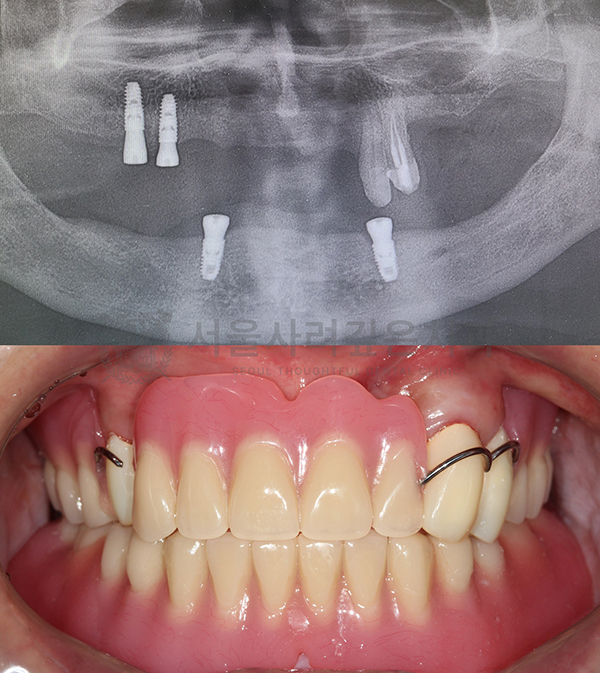

보철까지 고려한 디지털 임플란트

임플란트 클리닉

임플란트에 시술에 있어 가장 중요한 것은

‘최종 보철물의 위치와 형태’입니다.

서울사려깊은치과에서는 임플란트의 최종 보철물을 먼저 설계하고,

그에 맞춰 임플란트의 식립 위치와 각도를 결정하는 것을

원칙으로 합니다.

-

3D CT와 구강 스캐너를 통한

정밀한 시뮬레이션

사전에 제작된 수술 가이드를 통한

네비게이션 가이드 수술

디지털 네비게이션

임플란트

디지털 기술을 이용해 정교한 3D 모델을 만들고

정확한 위치에 임플란트를 식립하여

높은 정밀도로 맞춤형 치료를 제공합니다.

보철 중심의

임플란트 설계

최종 보철물(크라운, 브릿지 등)의

위치와 형태를 먼저 설계한 뒤,

그에 맞춘 최적의 위치에 임플란트를 정확히 심는

탑다운 치료 계획(Top-Down Planning)을 적용합니다.